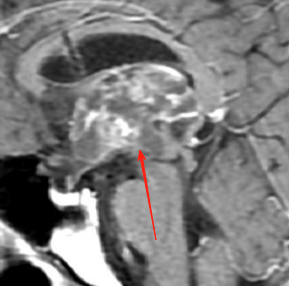

“病灶位于脑干,这不是普通的脑部手术。”拥有30多年脑干手术经验的巴特朗菲教授详细评估道,“如果用1到10分来评估手术难度,这台手术大概在5到6分左右。”面对着这个常常被成为“手术禁区”的延髓位置,巴教授显得从容不迫:“有些神经外科医生可能会认为这类手术无法进行,或者风险极高。但我一直在做这类手术。”巴教授不仅详细解析了手术入路选择、手术操作要点,还就术中神经监测、术后康复管理等关键环节进行了解答。

和巴教授同为德国人的Z先生,长期在中国生活。当不幸查出“延髓背侧占位”,虽然已经咨询过多个国家的神经外科医生,巴教授的回复让Z先生对于手术充满信心,最终选择在亚洲神经外科临床、科研、教学基地——北京天坛医院接受巴教授主刀的手术。